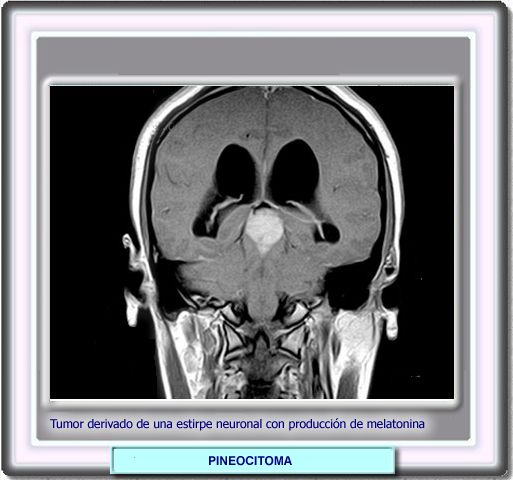

Los tumores más frecuentes de la región pineal son los disgerminomas que representan el 50% de todos los carcinomas de esta región y que no hay que confundir con los tumores pineales verdaderos (pineocitomas y pineoblastomas). Todos los tumores de la región pineal se manifiestan por la asociación de hidrocefalia e hipertensión intracraneal debida al bloqueo del acueducto.